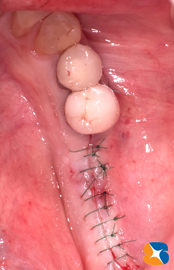

先日2/7(抜歯&骨の増設治療を済ませてから3ヶ月後)、点滴を使ってインプラントの手術を行いました。骨質は柔らかかったものの、骨の再生は無事に行われていました。

点滴および治療開始から2時間後、無事に手術は終わりました。